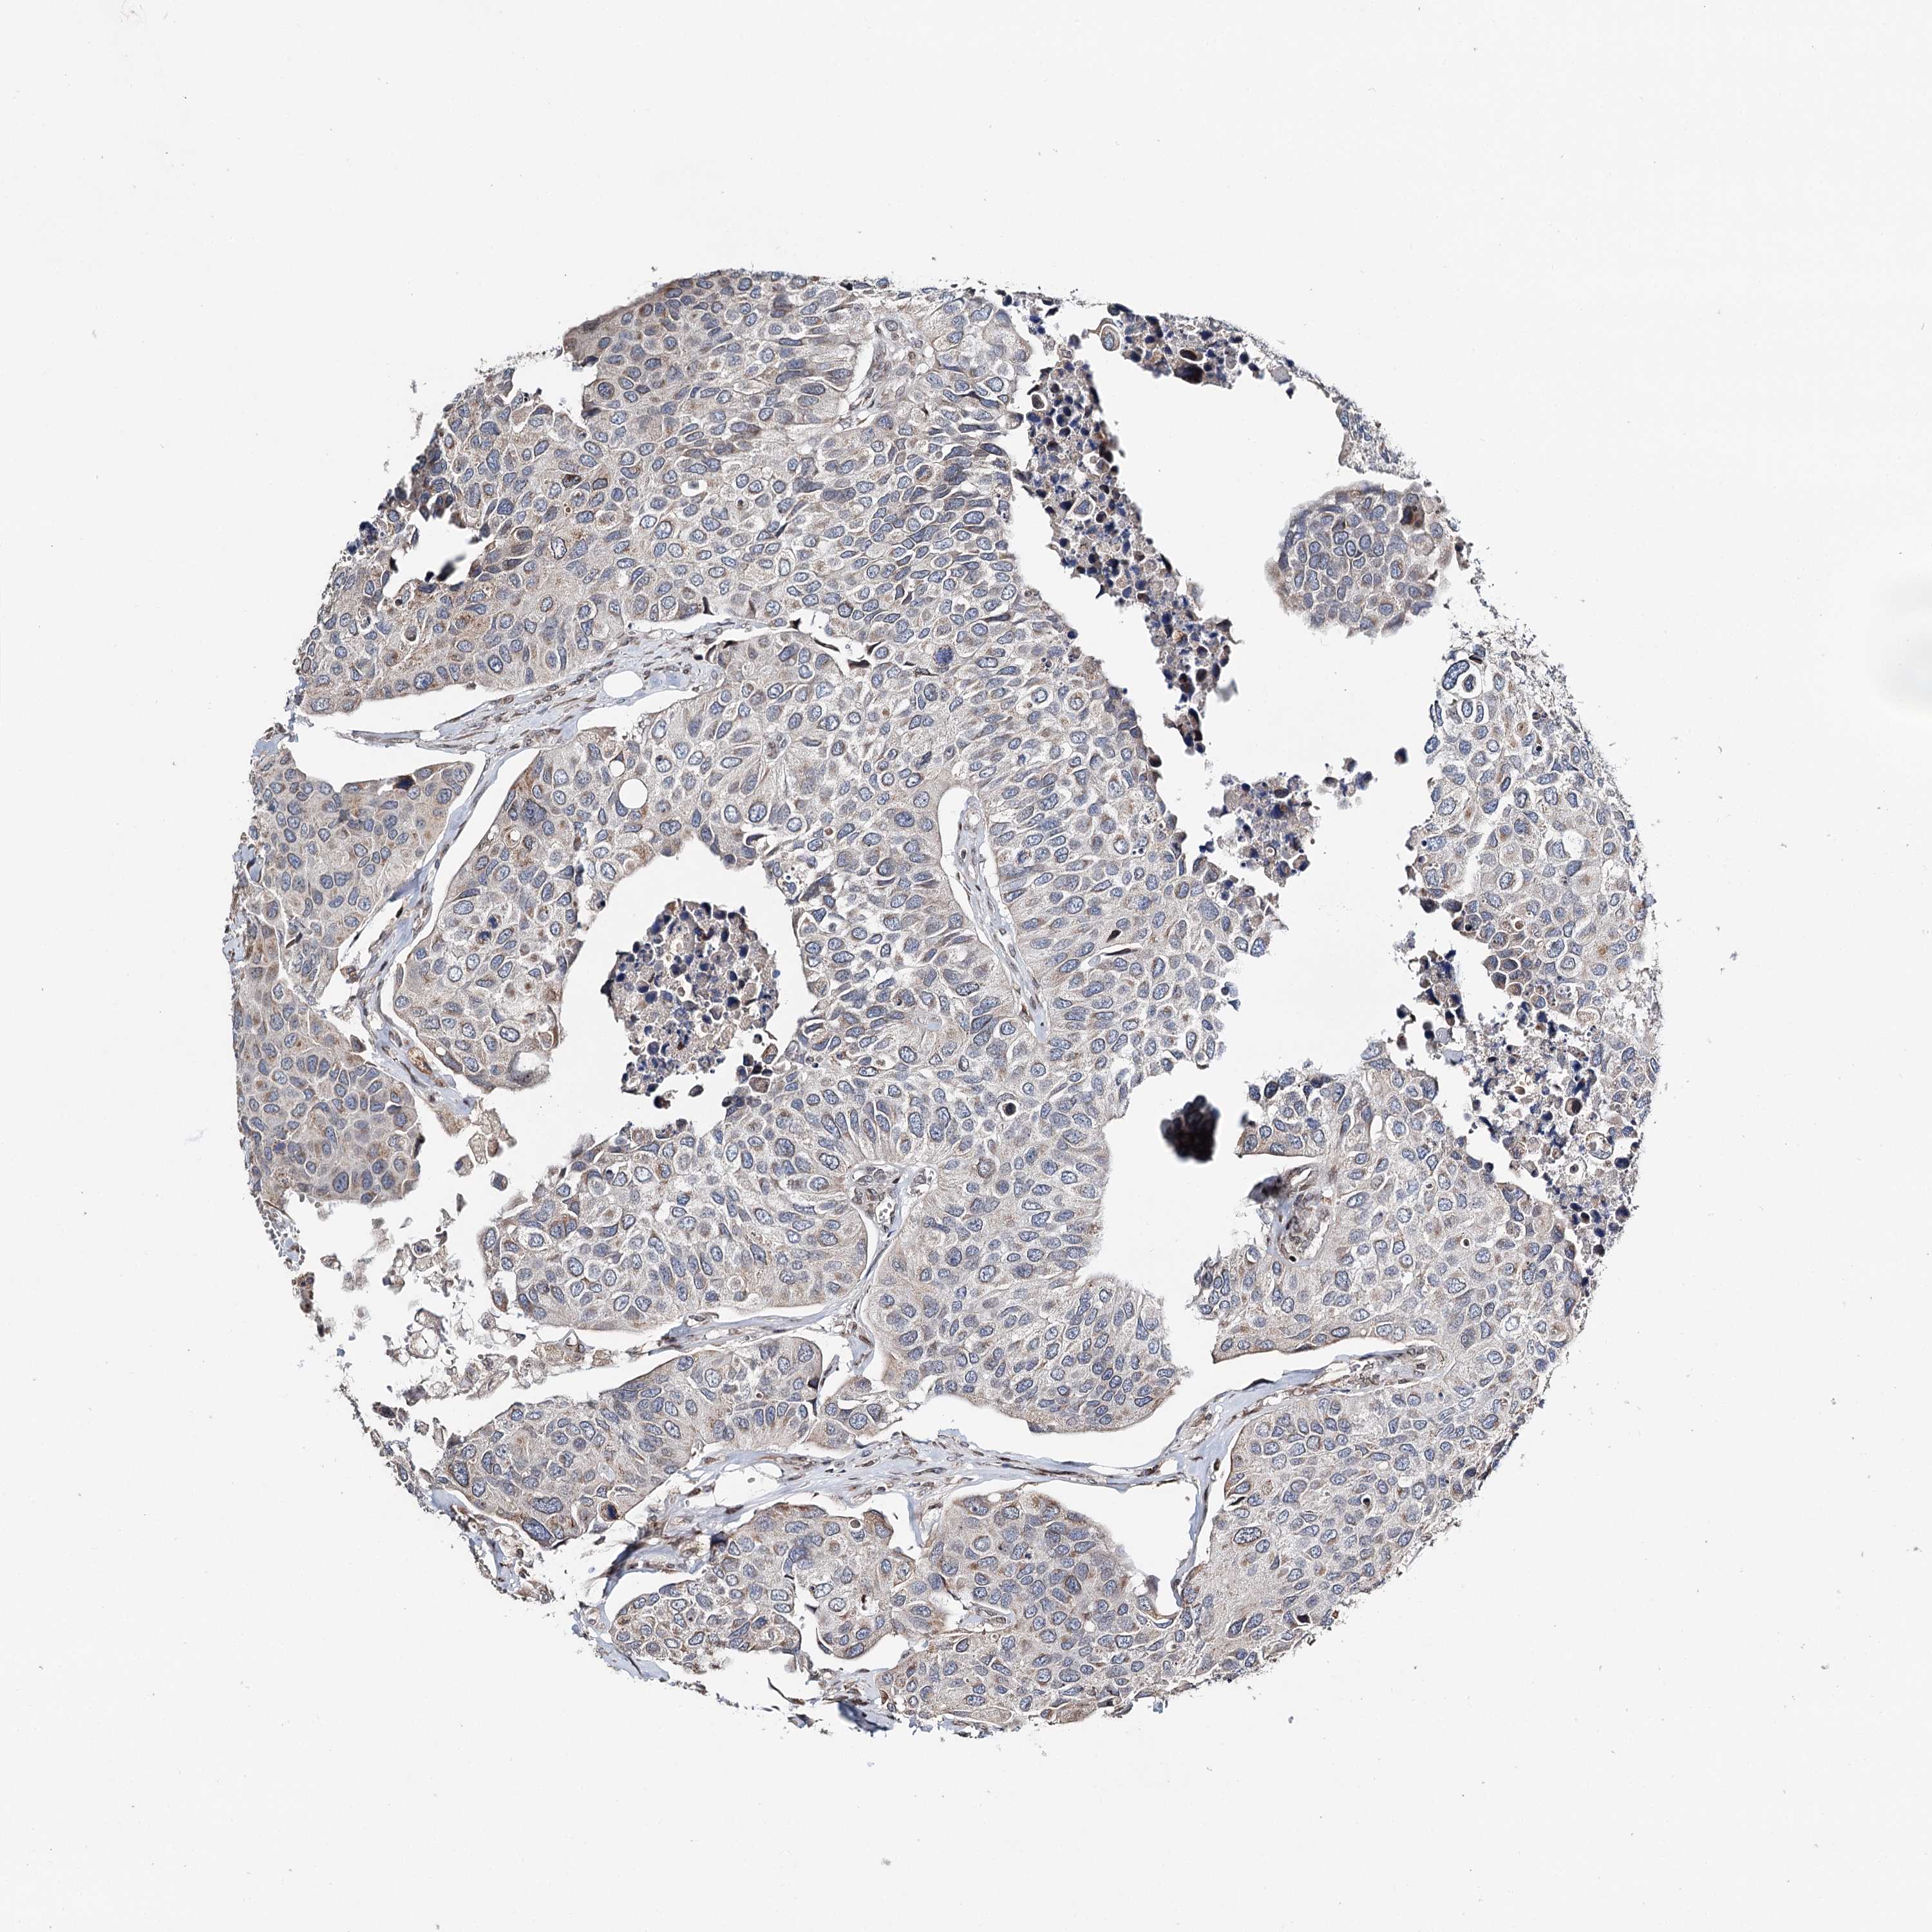

UROTHELIAL CANCER - Protein expressioni

A mouse-over function shows sample information and annotation data. Click on an image to view it in a full screen mode. Samples can be filtered based on level of antibody staining by selecting one or several of the following categories: high, medium, low and not detected. The assay and annotation is described here.

Note that samples used for immunohistochemistry by the Human Protein Atlas do not correspond to samples in the TCGA dataset.

Antibody stainingi

Antibody staining in the annotated cell types in the current human tissue is reported as not detected, low, medium, or high, based on conventional immunohistochemistry profiling in selected tissues. This score is based on the combination of the staining intensity and fraction of stained cells.

Each image is clickable and will lead to virtual microscopy that enables deeper exploration of all samples and also displays staining intensity scores, fraction scores and subcellular localization as well as patient and tissue information for each sample.

Antibody HPA037786

Antibody HPA038034

Antibody HPA038867

Antibody HPA038868

Staining

High

Medium

Low

Not detected

Intensity

Strong

Moderate

Weak

Negative

Quantity

>75%

75%-25%

<25%

None

Location

Nuclear

Cytoplasmic/membranous

Cytoplasmic/membranous,nuclear

Urothelial carcinoma, High grade

Urothelial carcinoma, Low grade

Urothelial carcinoma, NOS